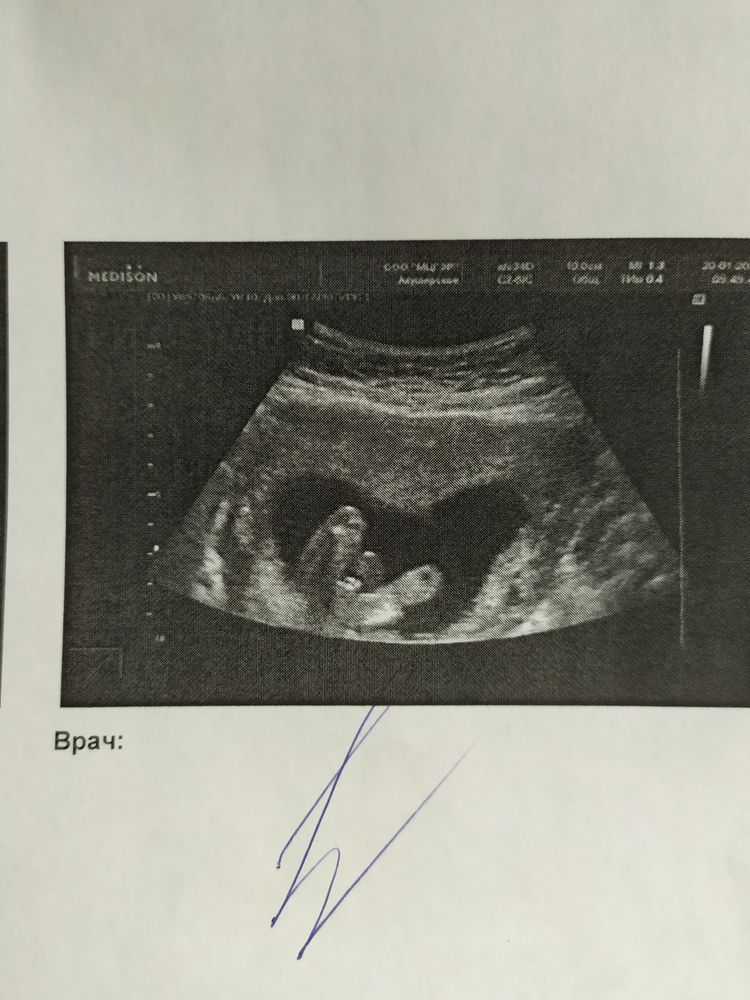

Экспертное УЗИ. Параметры плода Рубец в 35 недель